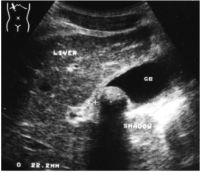

Picture2.

Acoustic

shadow.